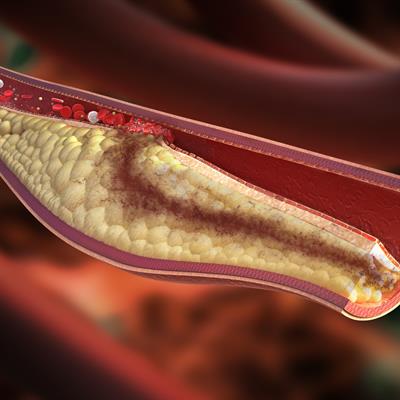

Challenges in the Contemporary Assessment of Coronary Physiology

- Dejan Orlic

- Milorad Tesic

- 16,269 views

- 6 articles